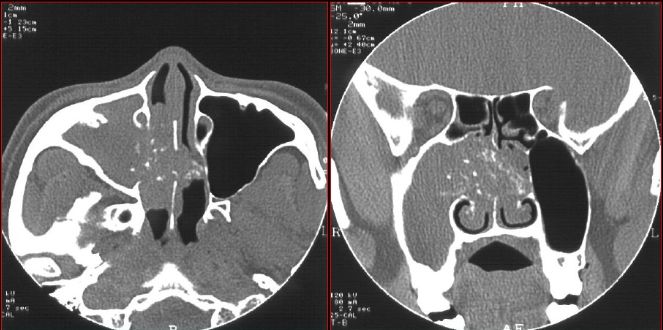

鼻窦炎—骨质改变

鼻窦炎—骨质增生

鼻窦炎—骨质增生及脑膜炎